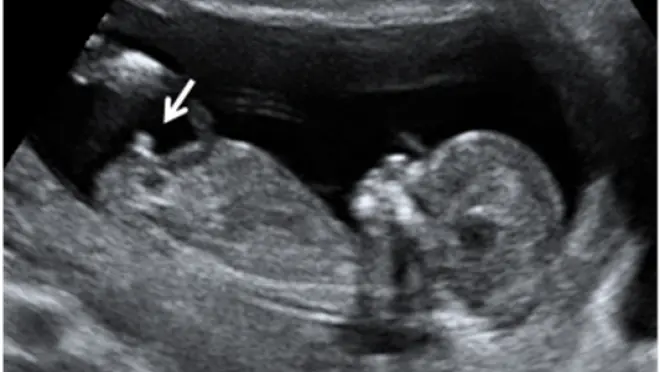

Revelación del Sexo Fetal

• ❤ Sabemos que conocer el sexo de tu bebé siempre será algo muy importante para ti, ¿Sabías que ya desde el primer trimestre podremos saber el sexo de tu bebé con una precisión de casi el 90%? A partir de la semana 16 ya se confirma el sexo en un 100%.

• ❤ La evaluación del sexo nos permitirá conocer algunas alteraciones de los genitales.

• ❤ Es importante también para descartar alteraciones genitales o enfermedades ligadas al sexo.